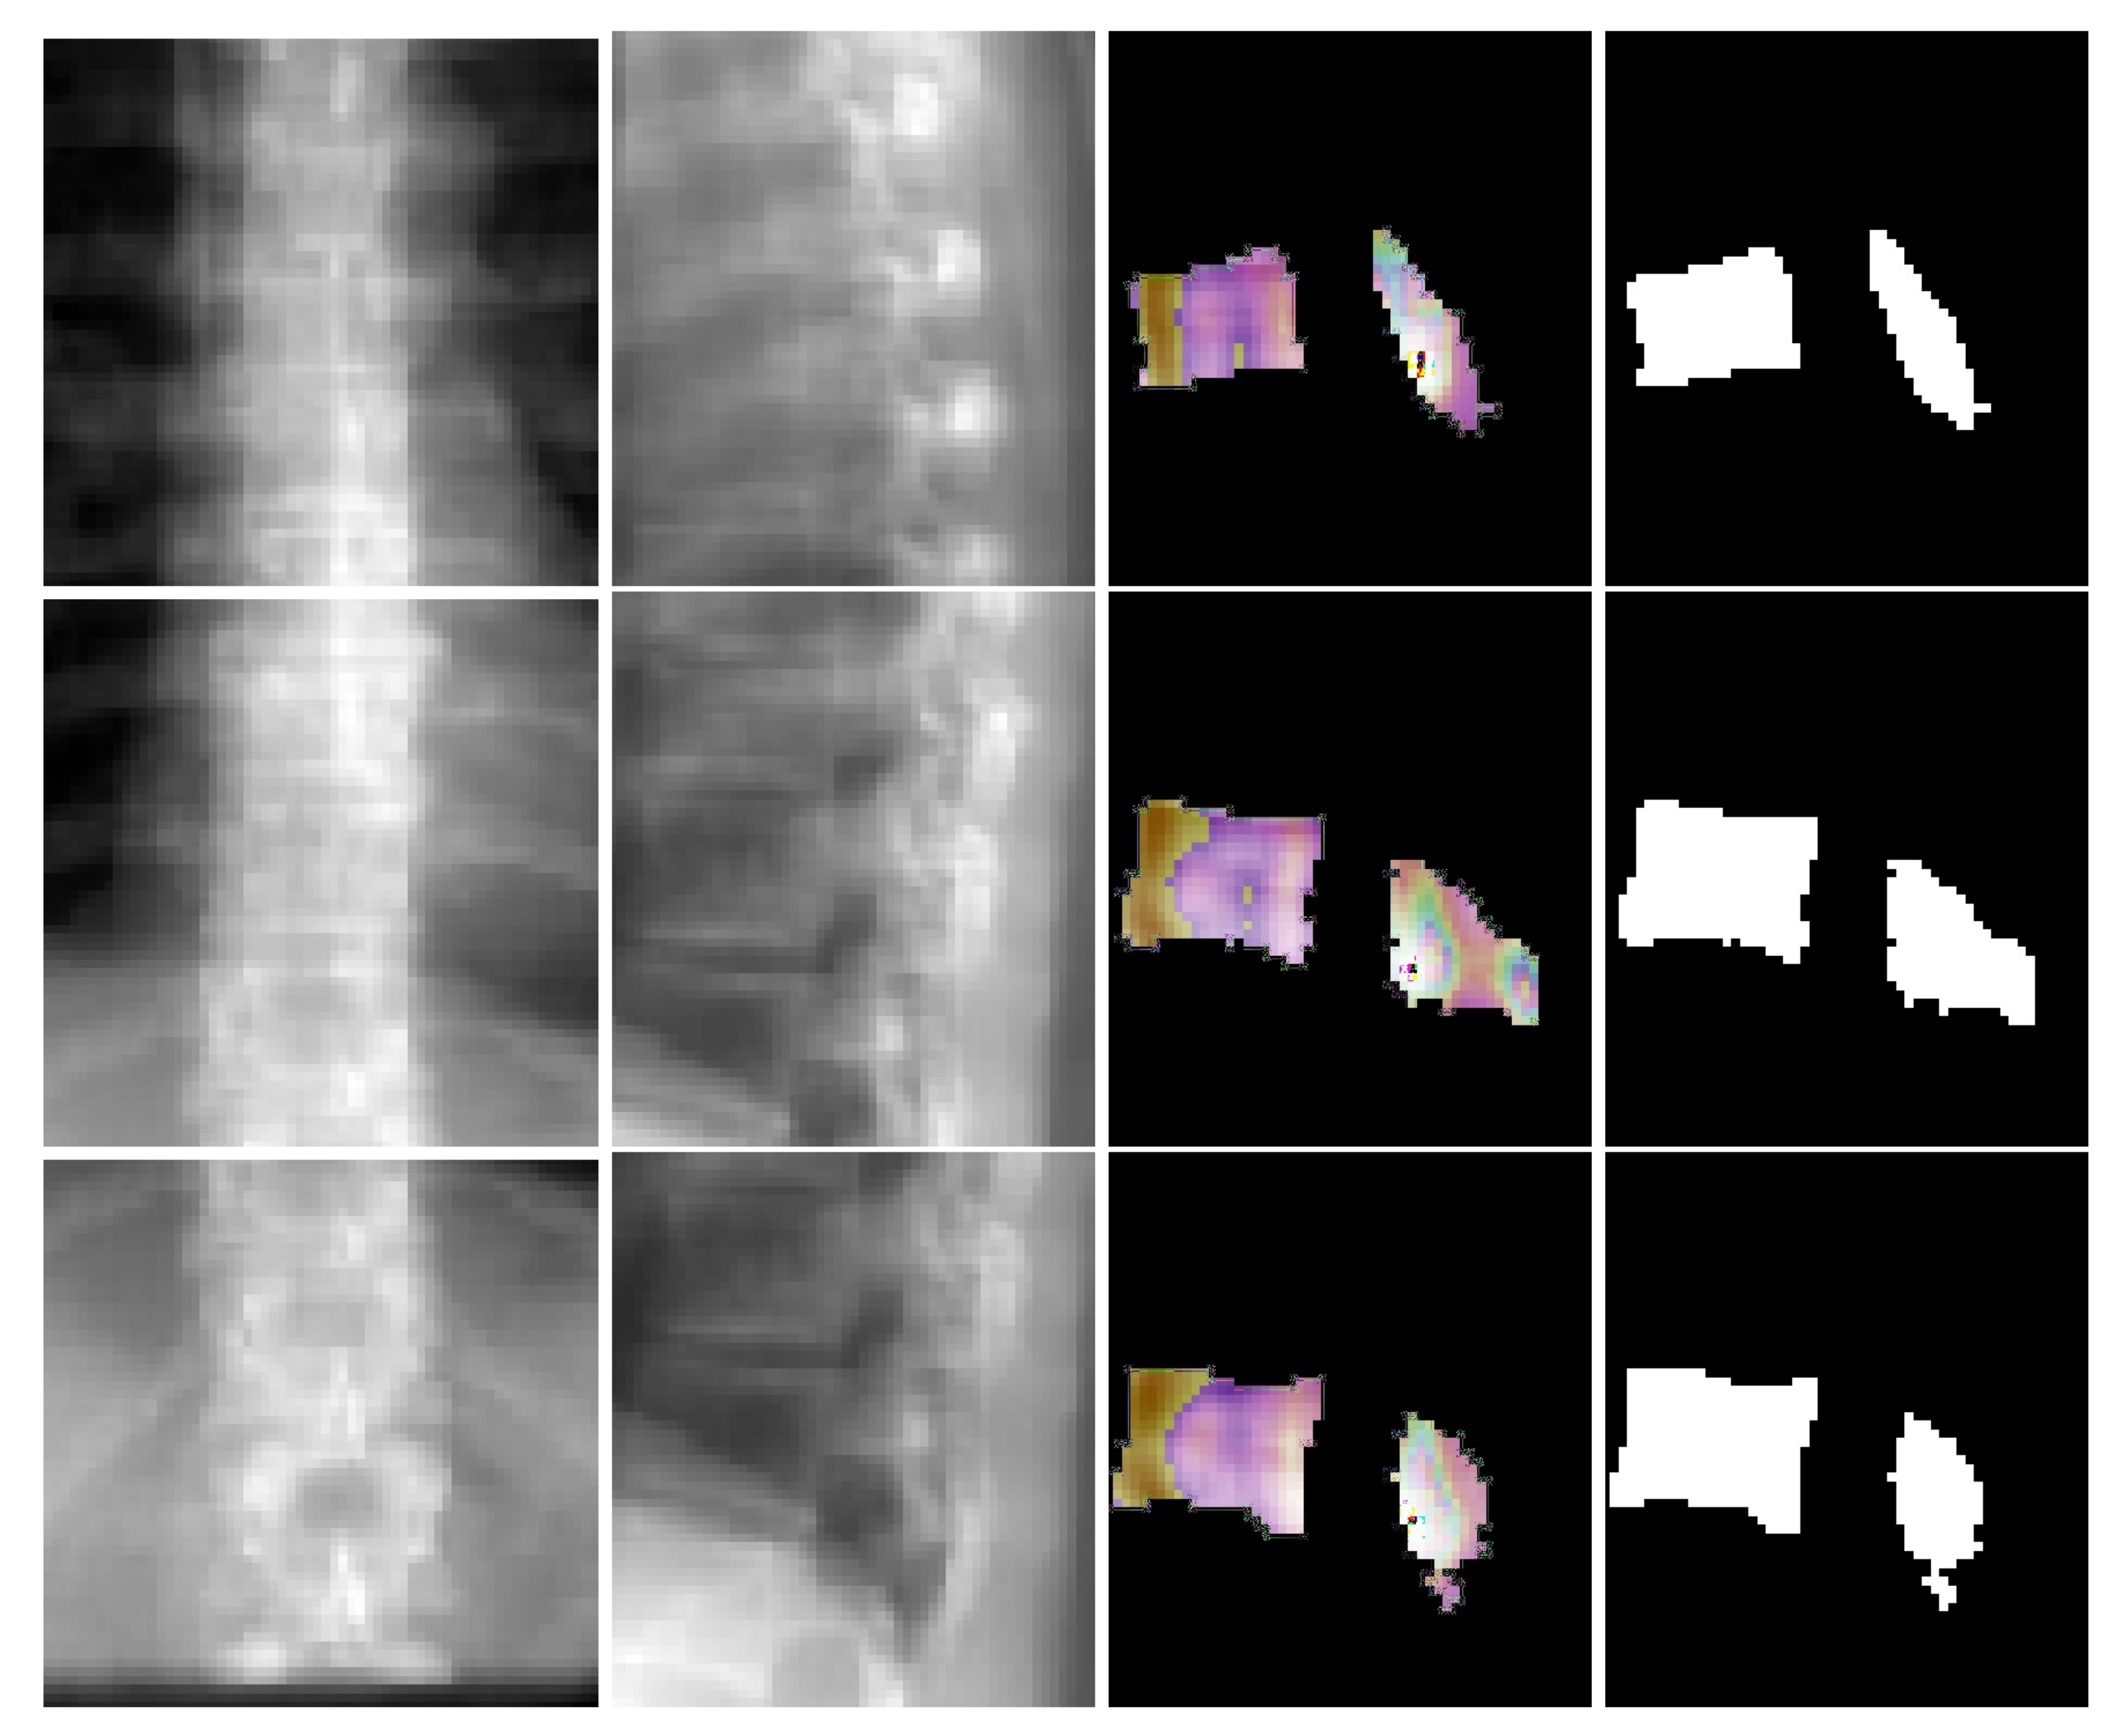

where G denotes the mapping performed by TransVert, x s and x c denote the 2D vertebral sagittal and coronal reformations; y s and y c denote the corresponding VOI annotations. The VOI-annotation image is obtained by placing a disc of radius 1 mm around the vertebral centroid. Figure 2 depicts orthogonal input image patches with corresponding centroid annotations, indicating the vertebra of interest in that patch. In [14], other annotation choices (vertebral body and full vertebral masks) are analyzed in several experiments. The TransVert model is trained on sagittal and coronal digitally reconstructed radiographs (DRR) created from CT images. The model is supervised by the corresponding CT images’ voxel-level, vertebral segmentation masks. Since DRRs are similar in appearance to real radiographs, a model trained on DRRs can be deployed on clinical radiographs.

Our network estimates the vector field that deforms a discrete atlas to the desired vertebral shape. We incorporate a spine atlas as a shape prior into our network architecture, to enforce vertebral shape constraints. We also define the spine curvature by atlas vertebral centroids, for enforcing the shape of the spine. In addition to image data, we include the vertebral labels as an additional annotation attached to the network input as depicted in Figure 2. We take a registration approach for shape synthesis and propose the TransVert+ network architecture.

Figure 6 depicts coronal and sagittal image patches from three vertebrae, mid-slice of the resulting estimated displacement field and vertebral shape. In the estimated displacement field the brighter colors indicate greater displacements. Figure 7 shows an example point cloud (with 2048 points) from the predicted and ground truth shapes, along with a point-wise Chamfer distance map. Observe that the vertebra’s posterior region (vertebral process) is hardly visible in the image inputs. In spite of this, TransVert+ was able to reconstruct the 3D shape of vertebral processes. To calculate the Chamfer distance map for each point in the reconstructed vertebra’s point cloud, the nearest point in the ground truth point cloud is found and the square of distance is depicted. Figure 8 illustrates a 3D spine reconstruction based on 2D DRRs.

Figure 6. Visualization of coronal and sagittal image patches from three vertebrae. First and second columns are the coronal and sagittal image patches, third column shows one slice of the predicted deformation field and last column is the corresponding slice in the resulting shape.